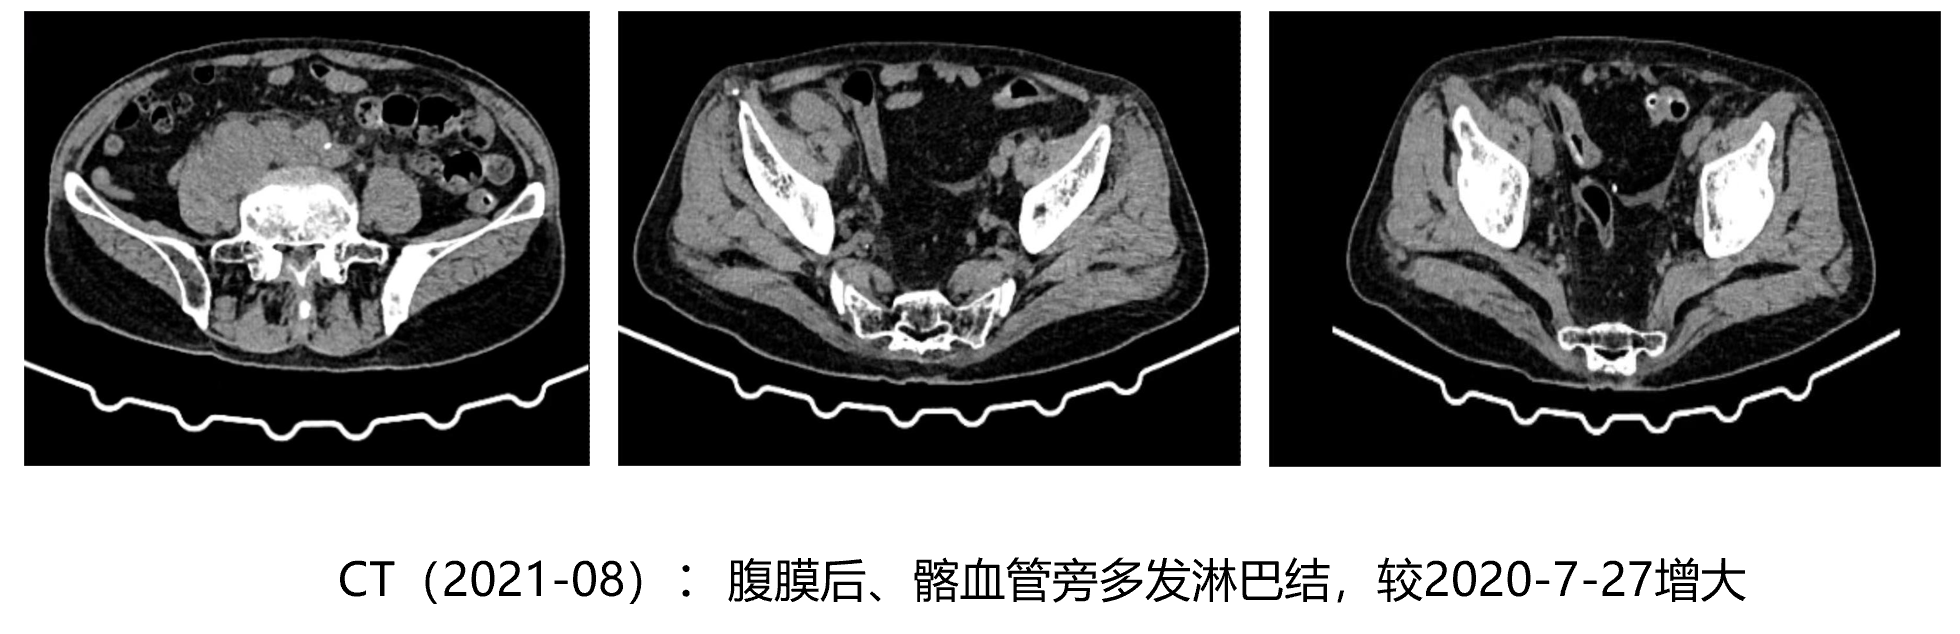

• CT(2020-07):肺部、肝脏等脏器转移未见转移,腹膜后及髂血管旁见少量肿大淋巴结

• 2020年12月-2021年8月: 亮丙瑞林+阿比特龙+泼尼松+唑来膦酸

• 2021年8月-10月: 亮丙瑞林+阿比特龙(原研)+唑来膦酸+塞来昔布/羟考酮

• 2021年10月:恩扎卢胺+PARPi+地舒单抗 120mg 皮下注射

影像学评估